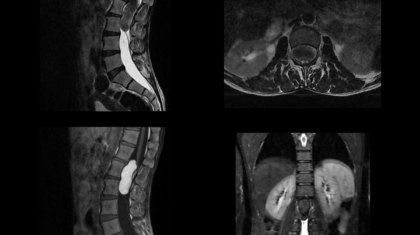

45 YEAR OLD MALE, Presenting compaints: Patient presented with lower back pain since 5 years;  right leg numbness and tingling since 6 months and acute onset urinary incontinence